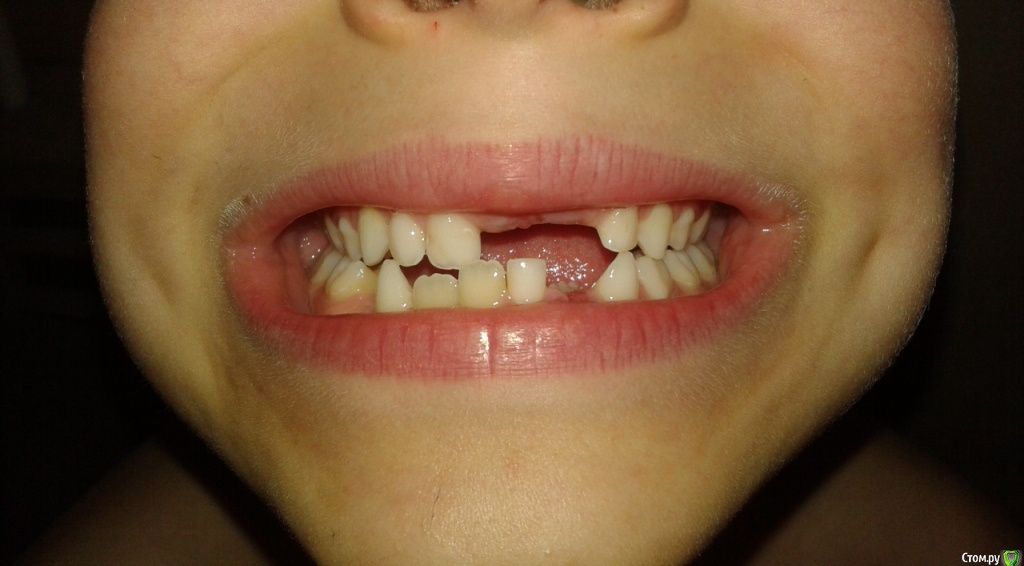

На сегодня ребенку 7 лет и у него вылезли все три коренных нижних зуба, но остался еще один нижний молочный зуб в этом ряду.

Вопрос состоит в том, что делать с этим молочным нижним зубом.

Пока ничего не делать.Когда нет зачатка постоянного молочные стоят относительно долго, во взрослом возрасте ( после 20 лет примерно)  или когда начнет шататься удалить и имплант.